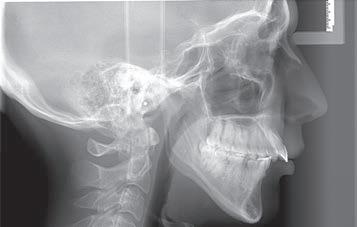

Figs. 1a–h: Initial situation: patient’s facial view (a-c); intraoral view (d-f); cephalometric X-ray (g); pantomograph X-ray (h).

A female, age 23 years, 5 months, presented for treatment exhibiting a moderate Class III malocclusion with negative overjet, proclined lower lip with flat supramentale sulcus, open bite and crowding in the lower arch. The treatment plan was to distalise the lower dentition into a Class I occlusion (Sagittal First) using the Carriere Motion CL III Appliance, then generate space to alleviate the lower arch crowding and close the bite, utilising light-force archwires in a passive, self-ligating system. While tongue trainers would be bonded in conjunction with the fixed appliances later in treatment, the patient would also engage in tongue training exercises to correct her improper